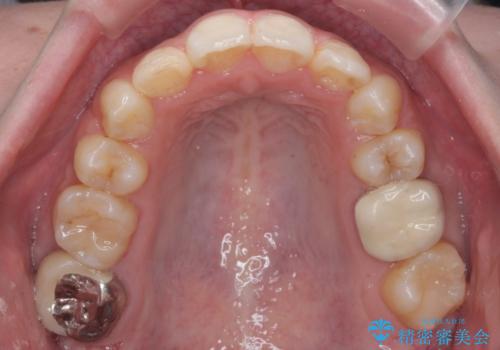

- 前歯のがたつきを主訴に来院。

顔が小さく、顎に大きな歯が入りきらない状態でした。

抜歯してワイヤー矯正を行いました。

治療に時間はかかりましたが、喜んでいただけました。

矯正後は口も閉じやすくなり、大変喜んでいただけました。